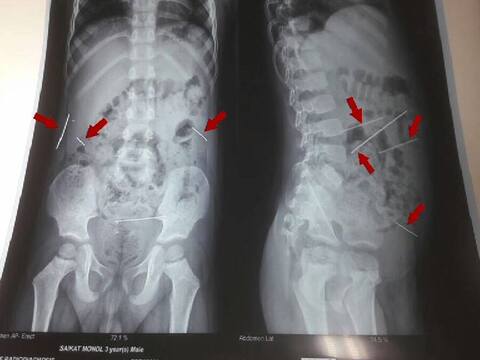

বীরভূম: পুরুলিয়ার পর এবার বীরভূম। গত বছর লাভপুর থেকে এসএসকেএমে আনা শিশুর শরীরেও মিলেছিল ৪টি সূচ। নেপথ্য তন্ত্রসাধনা বা ঝাড়ফুঁকের মতো বিষয় থাকতে পারে বলে অনুমান। সেবারও মুখ খুলতে চায়নি শিশুর পরিবার। এবারও পুরুলিয়ার শিশুকন্যার মায়ের মুখে কুলুপ। এ যেন যন্ত্রণার পুনরাবৃত্তি!সেই একই কায়দায় ছোট্ট শরীরে নির্মম অত্যাচার! সূচকাণ্ড আগেও ঘটেছে.....পুরুলিয়ার মফস্সল থানা এলাকা থেকে ১৮০ কিলোমিটার দূরে বীরভূমের লাভপুরে। ঠিক এগারো মাস আগে, ২০১৬-র অগাস্টে। বীরভূমের লাভপুরে একই কায়দায় অত্যাচারের শিকার হয়েছিল এক শিশুপুত্র। তিন বছরের শিশুর পেটে ঢোকানো ছিল ৪টি সূচ! তাকেও এসএসকেএমে ভর্তি করা হয়েছিল। পুরুলিয়ার মফস্সল থানা এলাকার বাসিন্দা একরত্তি মেয়েটার শরীরে ঠিক যেভাবে সূচগুলি ঢোকানো হয়েছে....ঠিক সেই ভাবেই লাভপুরের ওই শিশুর পেটে ঢোকানো হয়েছিল ৪টি সূচ! সেবার অস্ত্রোপচার করে শিশুটিকে সুস্থ করে তোলেন এসএসকেএমের চিকিত্সকরা। এবার পুরুলিয়ার শিশুর চিকিৎসাও চলছে সেই এসএসকেএমে!পুরুলিয়ার ঘটনা নিয়ে মুখ খুলতে চায়নি শিশুকন্যার মা। বীরভূমের লাভপুরের ঘটনাতেও মুখ খুলতে চাননি অভিভাবকরা। পুরুলিয়ার ঘটনায়, ৩ বছরের শিশুকন্যা মায়ের আশ্রয়দাতার বিকৃত যৌন লালসার শিকার হয়েছে বলে অভিযোগ। নেপথ্য তন্ত্রসাধনাও থাকতে পারে বলে অনুমান পুলিশের। এই প্রেক্ষাপটে লাভপুরের ঘটনার ক্ষেত্রেও এরকম কিছু ঘটেছিল বলে সন্দেহ। ২ ঘটনার মধ্যে পরতে পরতে মিল। সেবারও নির্মম অত্যাচার নেমে এসেছিল ৩ বছরের এক শিশুপুত্রর ওপর। এবারও সূচবিদ্ধ পুরুলিয়ার ৩ বছরের শিশুকন্যার শরীর।